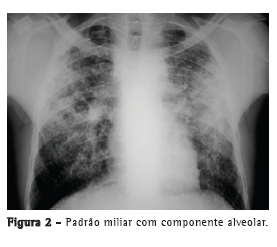

Com relação aos achados radiológicos, infiltrados reticulares e consolidação são os padrões mais frequentes,(5,6,10,15,17) sendo que cavitação pode estar presente em 27-50% dos casos.(6,10,16) As Figuras 1 a 4 mostram alguns dos principais padrões radiológicos nesse contexto.